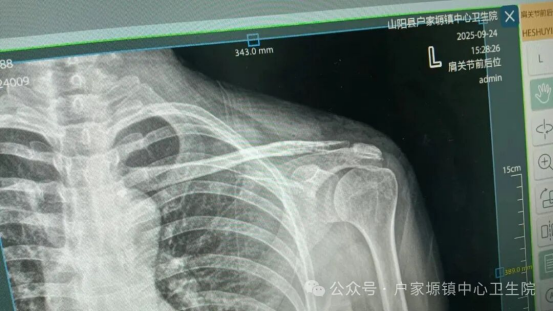

接诊后,外科团队第一时间为何女士完善检查,仔细分析其病史与影像学报告,确认已达到手术指征。为确保手术安全,团队基于技术优势反复研讨,制定了兼顾“精准操作”与“快速恢复”的个性化方案,同时耐心向何女士及家属讲解手术流程与术后注意事项,缓解她们的紧张情绪。